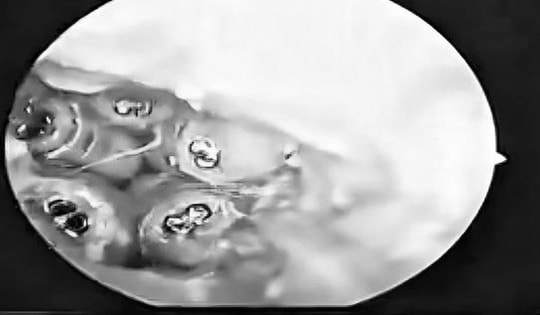

Cháu bé đau tai dữ dội, bác sĩ sốc ngang phát hiện bí mật "đáng sợ" bên trong

Cảm thấy ngứa tai rồi đau tai dữ dội, cháu bé đã đến tiệm cắt tóc để lấy dị vật nhưng không được, sau đó được người nhà đưa đến bệnh viện thăm khám. Bác sĩ bất ngờ gắp ra thứ "đáng sợ" bên trong.

Khi đang ngủ, người đàn ông 33 tuổi bị một con vật quen thuộc chui vào tai gây tổn thương niêm mạc, đau đớn dữ dội.